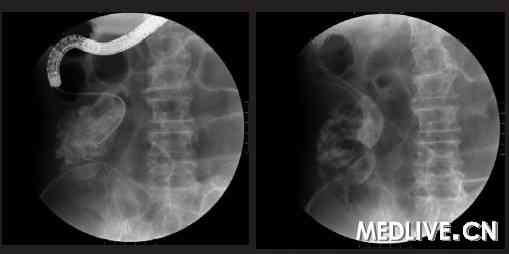

胸片、肺CT:心肺未见异常。全身骨扫描:未见异常代谢灶。腹平片:小肠扩张,可见多个液气平面(图1)。考虑不全性肠梗阻。

图1 治疗前腹部平片

(左图:立位,右图:卧位。箭头所示为肠梗阻扩张的肠袢)